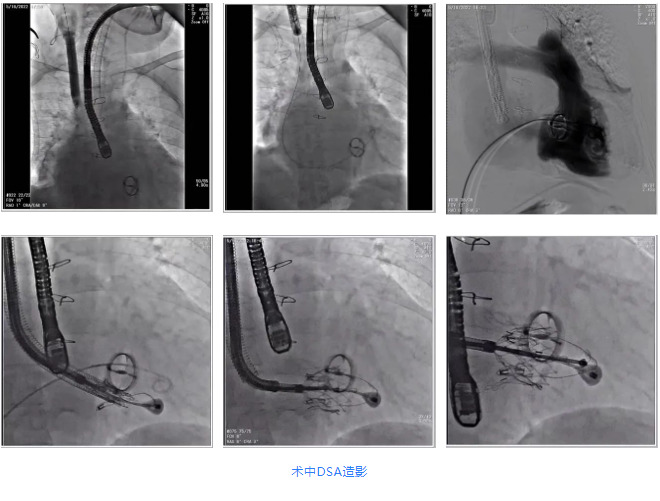

根據術前評估結果,郭應強教授團隊為患者量身定制了手術策略,決定使用LuX-Valve Plus經血管三尖瓣置換系統開展手術治療。手術在全麻下進行,采用經右側頸靜脈入路,在經食道超聲和DSA的指引下調整輸送器角度以達到正確位置,勾住前瓣后逐步釋放盤片,盤片打開后順利扎針,最終完成瓣膜植入,輸送器撤出。術后超聲提示人工三尖瓣同軸性良好,瓣架固定牢靠,無反流和瓣周漏,術后三尖瓣平均跨瓣壓差為1 mmHg。